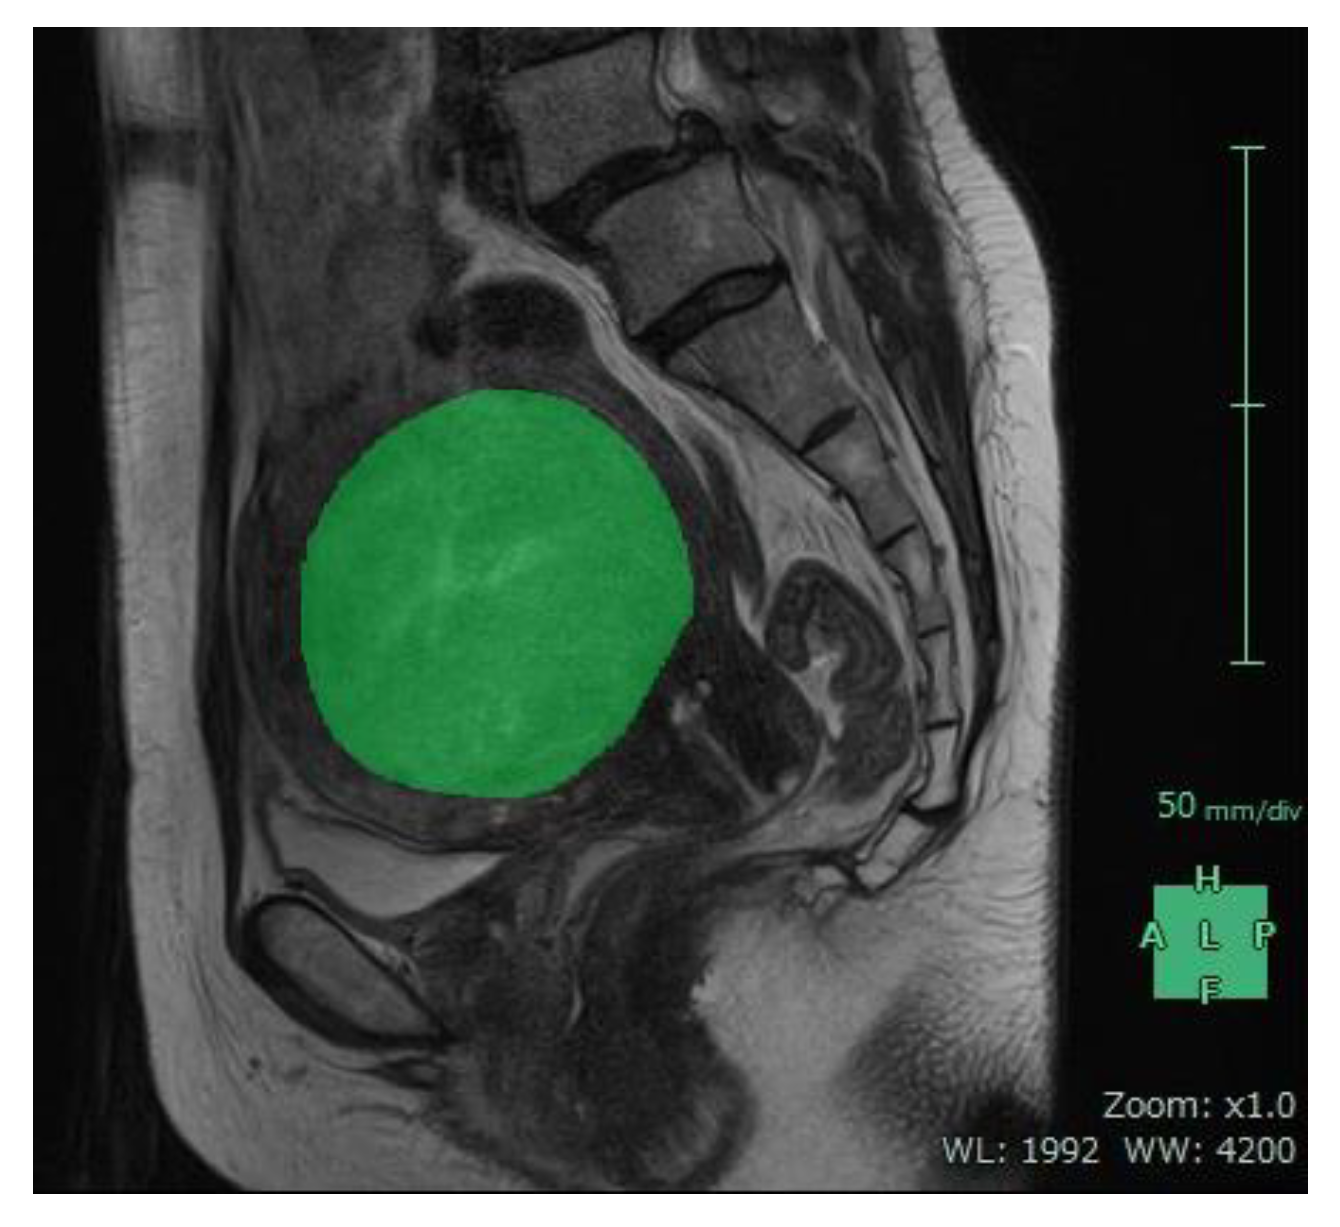

Figure 5.

Sagittal MR image from a 48-year-old woman obtained before uterine artery embolization. The margins of the uterine tumor were delineated in sequential sagittal slices similar to those shown in green (mask).